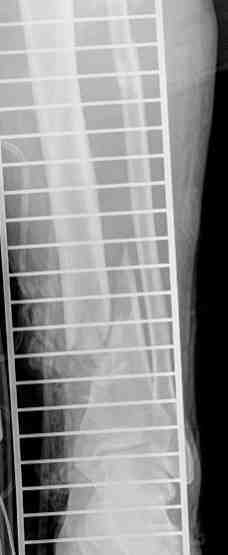

В верхнем ряду показаны рентгенограммы до, после коррекции и после снятия аппарата Илизарова.

On the upper row the X-rays of lt leg before correction, after correction and after apparatus removal have been showed.

В нижнем ряду представлены два снимка после коррекции деформации правой голени. Видно, что качество коррекции не зависит от квалификационного наложения аппарата Илизарова, что было специально произведено для проверки работы программы.

Lower two X-rays – rt leg after deformity correction. As you can see the quality of correction does not depend of placement of Ilizarov Apparatus